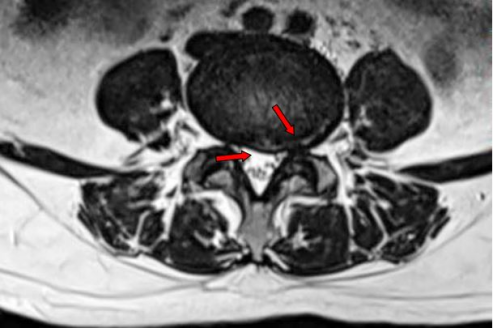

术前腰椎MRI显示椎间盘突出明显,侧隐窝狭窄 术中精准定位

术前腰椎MR 可见腰4/5椎间盘中央偏左后突出,左后侧纤维环严重变薄,仅剩最外层纤维环完整。左侧侧隐窝狭窄,相应节段神经根受压。

术后3个月复查腰椎MRI,对比相同节段相同层面的图像,可见纤维环回缩明显,局部侧隐窝狭窄减轻,椎管狭窄减轻。